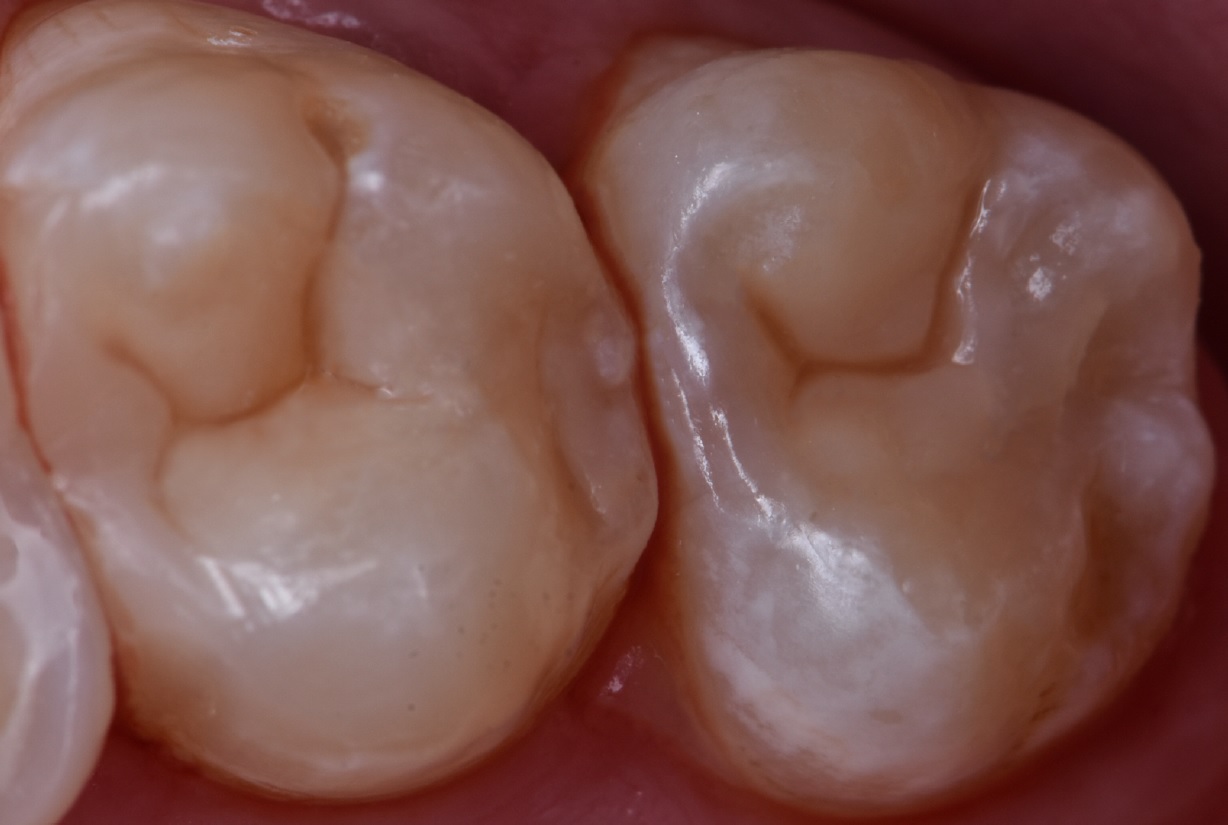

Εικ. 15: Η σύνθετη ρητίνη 3M™ Filtek™ Easy Match Shade N (Solventum) εφαρμόστηκε για την ενίσχυση του αισθητικού αποτελέσματος. Δεδομένου ότι είναι λιγότερο ημιδιαφανής από μια απόχρωση αδαμαντίνης, καλύπτει αποτελεσματικά το Biodentine XP, ενσωματώνοντας την αποκατάσταση με το φυσικό δόντι. Τέλος, όπως και με τον δεύτερο γομφίο, σχεδιάστηκαν οι απαραίτητες γραμμές για την αναπαραγωγή της μορφολογίας της μασητικής επιφάνειας με χρώση για να προστεθεί βάθος και μια πιο φυσική, τρισδιάστατη εμφάνιση της αποκατάστασης.

Εικ. 16: Τελική εικόνα μετά την αφαίρεση του ελαστικού απομονωτήρα και την τελείωση και στίλβωση της αποκατάστασης.

Εικ. 17: Η αρχική κατάσταση και το τελικό αποτέλεσμα και των δύο αποκαταστάσεων